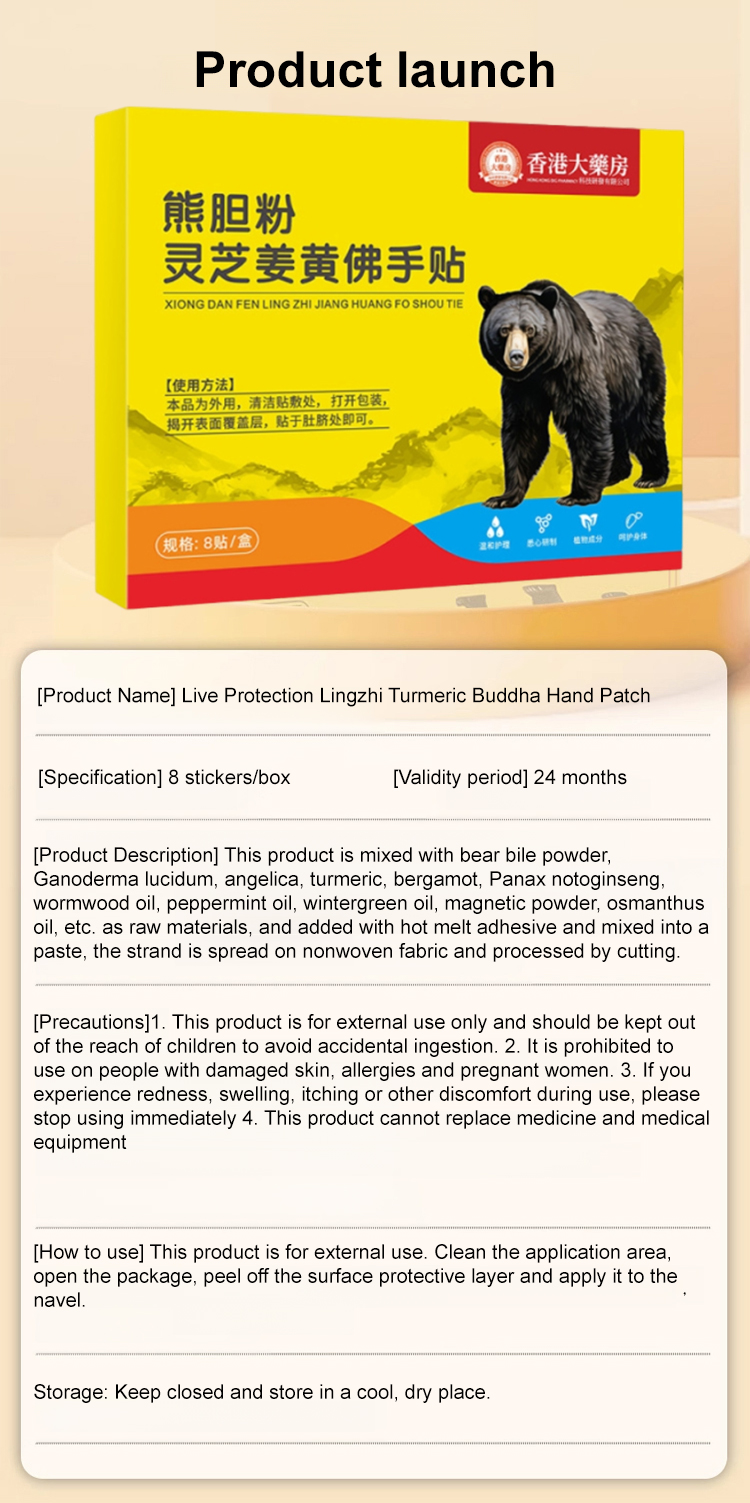

Hong Kong Pharmacy Liver Protecting Lingzhi Turmeric Buddha Hand Patch

$28.00 SGD

$56.00 SGD

Save $28.00 SGD